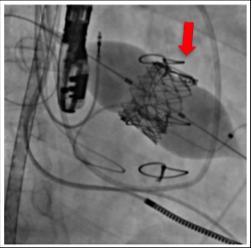

image: Transcatheter biologic valve implantation in the dysfunctional mitral prosthesis. view more

The Cardiovascular Surgery Group at Osaka University performed a transcatheter mitral valve implantation in dysfunctional artificial valves in severe cardiac failure patients with prosthetic valve dysfunction, which was previously thought to be incurable or high-risk, succeeding in improving the cardiac function of these patients. In the future, this technique is anticipated as a new therapy for the treatment of prosthetic valve dysfunction in patients with serious heart failure who are either inoperable or require a post-surgery auxiliary artificial heart.

This time, Prof. Sawa's group succeeded in transcatheter mitral valve implantation in patients with severe heart failure in clinical research for transcatheter aortic valve implantation (TAVI), a new therapeutic method which the group had actively performed. Because this therapeutic method has enabled minimally invasive treatment on patients who were previously regarded as being incurable or high-risk, it is highly anticipated as a new treatment method for prosthetic valve dysfunction in patients with severe heart failure.